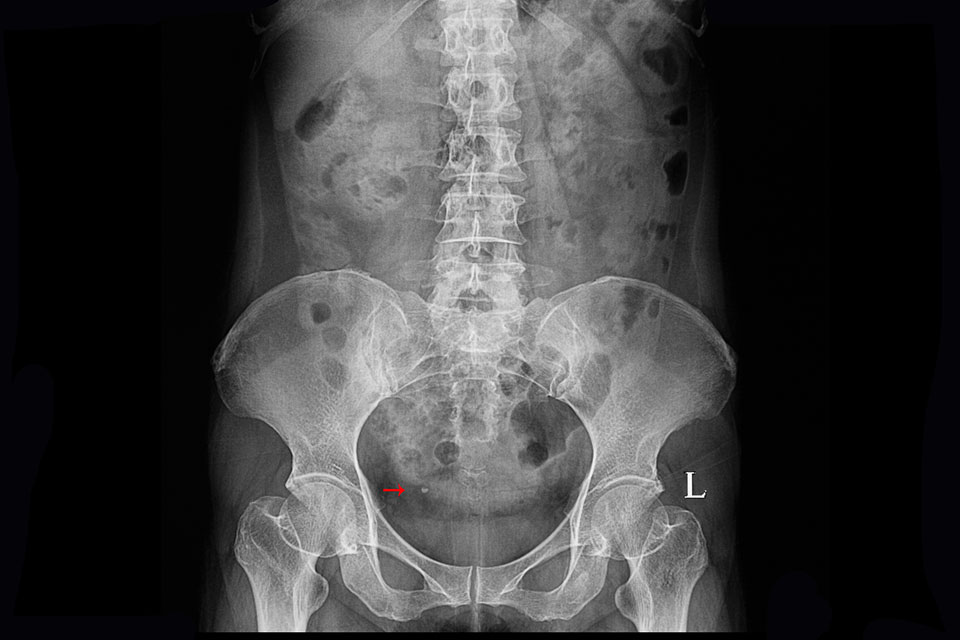

Causes urologiques : la cause principale de l’hématurie est une infection urinaire, laquelle s’accompagne de brûlures à la miction, de fréquentes envies d’uriner (pollakiurie) et de douleurs lombaires. Il peut s’agir d’une cystite (infection au niveau de la vessie), d’une pyélonéphrite (infection au niveau du rein et de l’uretère) ou encore d’une prostatite(infection au niveau de la prostate). Autres causes urologiques possibles : une tumeur du système urinaire (vessie, uretère) ou rénale, un traumatisme (lésion de la vessie, fracture du parenchyme rénal, conséquence de la pose d’un cathéter…) ou des calculs (lithiases) urinaires.

Pour diagnostiquer une hématurie, le médecin commence par échanger avec le patient (date de début des symptômes, fréquence, intensité, antécédents) puis il réalise un examen urinaire avec une bandelette pour détecter l’éventuelle présence de sang dans les urines. Il prescrit ensuite un ECBU pour préciser le diagnostic, de même qu’un examen du culot urinaire, c’est-à-dire du dépôt dû aux sédiments urinaires. Par la suite, d’autres examens vont venir éclairer la cause de l’hématurie constatée : une échographie de l’appareil urinaire (vessie, rein, uretère, urètre, prostate) ou uroscanner (examen plus précis que l’échographie dans le bilan de l’hématurie). Selon la cause identifiée, différents examens peuvent être nécessaires, comme une cystoscopie de la vessie, ou une ponction-biopsie des reins, par exemple.

Le traitement de l’hématurie dépend de la cause diagnostiquée. Ainsi, pour une cystite ou une pyélonéphrite, des antibiotiques spécifiques sont prescrits. Alors que pour des calculs urinaires par exemple, si l’expulsion spontanée n’a pas lieu, on peut envisager une fragmentation des calculs par des ondes de choc ou extraire les calculs rénaux par urétéroscopie (endoscopie par les voies naturelles, c’est à dire l’urètre, pour aller au contact du calcul pour le détruire et l’extraire), en plus de prescrire des antalgiques.